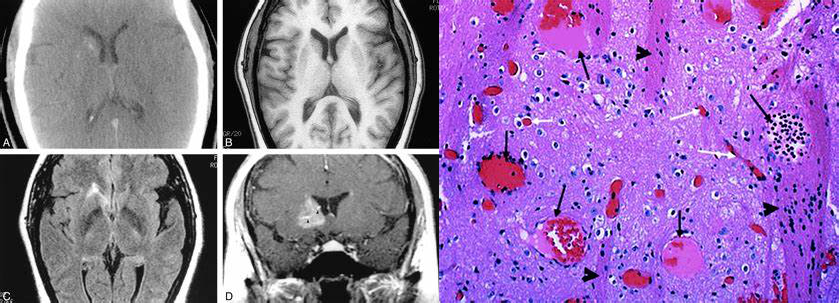

右侧基底节区较大毛细血管扩张症,CT 呈稍高密度,MR 增强呈片状稍淡样强化,可见引流静脉,镜下可见扩张的毛细血管,异常血管之间可夹杂脑组织

镜下由缺乏平滑肌细胞和弹性纤维的扩张毛细血管壁构成,异常血管之间可夹杂脑组织,部分灶周可见胶质增生与陈旧性出血所致的含铁血黄素沉积,毛细血管扩张症有时候与海绵状血管畸形及静脉发育不良并存。但应注意,本病与遗传性毛细血管扩张症无关。

可见异常扩张的毛细血管,其间夹杂着正常脑组织